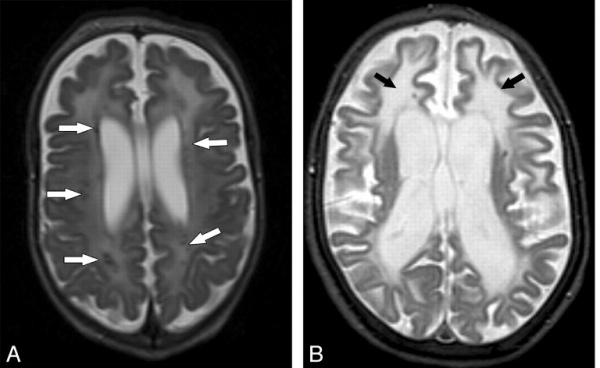

- МРТ головного мозга. Визуализирует полное или частичное недоразвитие мозолистого тела, признаки корковой атрофии, пахигирию, расширение борозд. III желудочек расширен, вместе с боковыми желудочками смещен вверх, вокруг него выявляются церебральные кисты. Отмечается изменение формы латеральных желудочков, множественные области гетеротопии с отсутствием дифференцировки слоев коры, гидроцефалия.